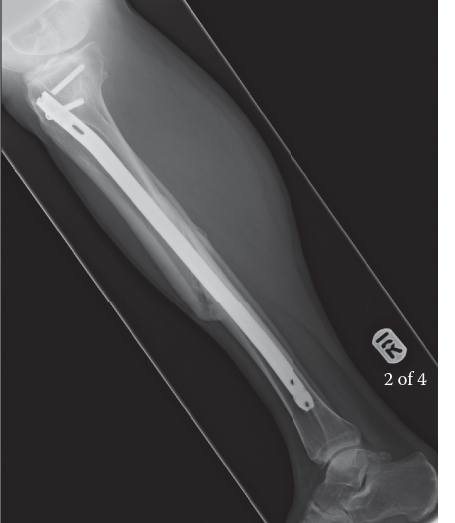

1.Describe the radiograph and explain the diagnosis. This is a lateral radiograph showing a tibial shaft fracture treated with an intramedullary nail. The nail is backing out and the proximal screw is clearly broken. The fracture shows no evidence of healing 12 months post-surgery and therefore this would be described as a non-union.

I would start by investigating for infection with a thorough history (as per Q3) and performing a full set of blood tests including FBC, ESR and CRP. If there was no infection, a non-union of the tibia can be treated very effectively with an exchange nailing with a nail 1–2 millimetres larger in diameter after reaming, and I would send reamings for microscopy, culture and sensitivity to rule out an indolent infection. As above, the increased diameter nail will lead to increased stabilisation of the fracture site and the reaming will deliver autologous bone graft to the fracture site.

The largest cohort of tibial diaphyseal non-unions treated with exchange nailing comes from Edinburgh and, in the aseptic cases, showed a union rate of 75% with a single exchange nailing, rising to 95% with repeat exchange nailing. In the context of infection, exchange nailing had a union rate of 35%, rising only to 61% after a second exchange nailing. Other methods of treatment, such as Ilizarov frames, are therefore indications in infected non-unions.

The radiograph below shows a successful union following exchange nailing.